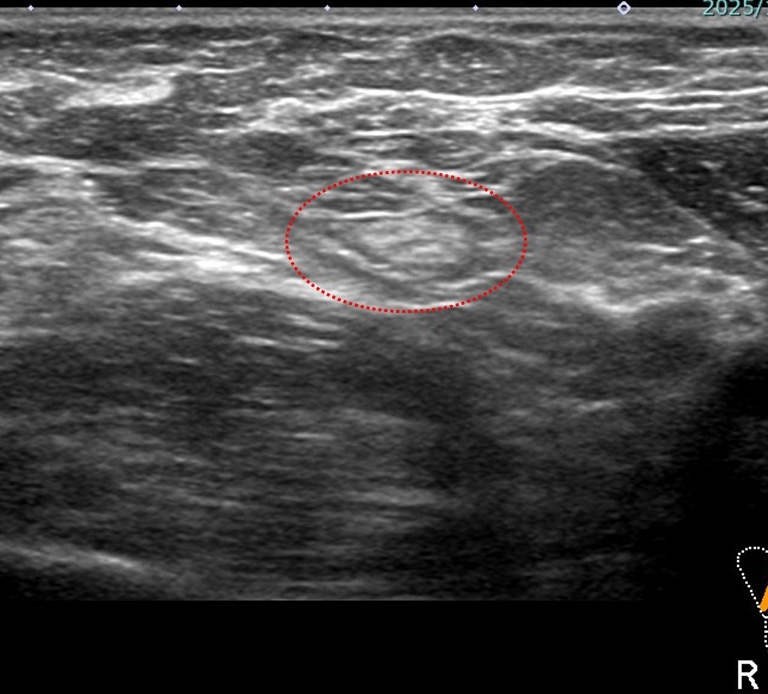

2.術前針生検の診断「非浸潤がん」と 手術病理「浸潤がん」の乖離

術前針生検で非浸潤がんだったのが、実際は(手術病理) 30mm overの浸潤がんだった。

♯ 非浸潤がん+浸潤がんも浸潤がんの大きさ=浸潤径と同じだった

つまり非浸潤がんのあるところには全て浸潤がんも存在

手術病理ではその「非浸潤がんの部分のみで診断、浸潤がんに気づかなかった(もしくは)浸潤がんを伴っていない部分に「たまたま」針生検があたった

このエコー像だと乳頭(画面左上)から乳管内を増殖(画面右方向へ)しているように見える

腫瘤形成していても、乳管内で広がることで浸潤していない場合もある

★ただし、同じ「術前組織診で非浸潤がん」でも (しこりのない)「石灰化のみ」で見つかるケースでは、やはり「手術しても非浸潤がん」というケースが多くなる